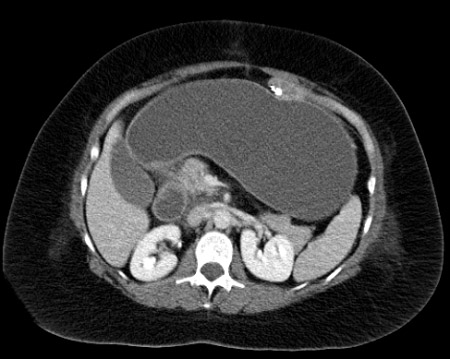

[Figure caption and citation for the preceding image starts]: Tomografia computadorizada (TC) do abdome no mesmo paciente revela um remanescente gástrico extremamente dilatado. Com orientação da TC, um remanescente dilatado é facilmente acessado por via percutâneaDo acervo de Daniel M. Herron, MD [Citation ends].